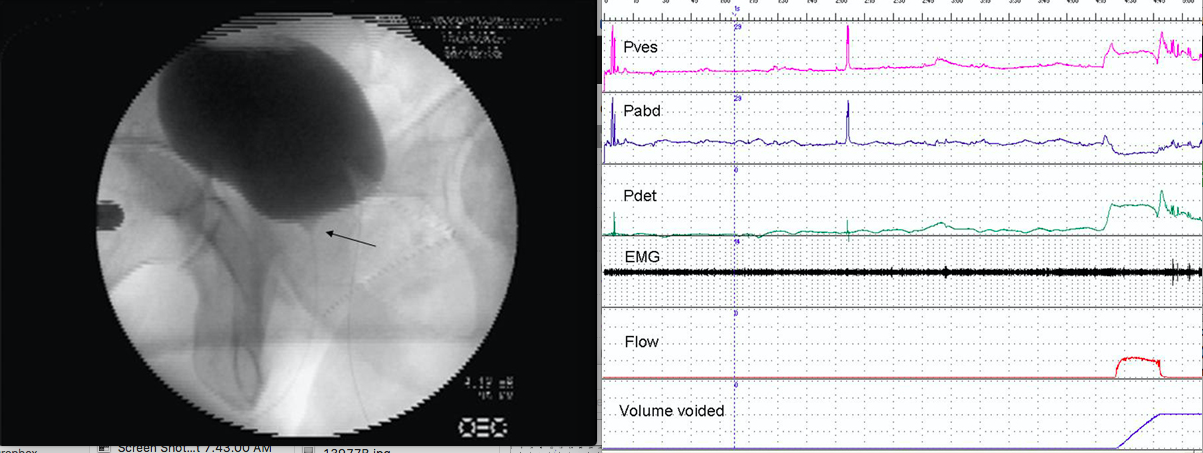

A 45-year-old neurologically normal man has worsening urinary incontinence for several years. Videourodynamic study is shown with the voiding image. The diagnosis is:

5

The urodynamic tracing indicates detrusor overactivity associated with incontinence and bladder outlet obstruction during emptying. The tracing does show increased EMG activity during the detrusor overactivity but this is due to volitional suppression, not true striated dyssynergia. The image demonstrates narrowing at the proximal urethra consistent with bladder neck obstruction with voiding. At the time, the voiding image is taken there is no increased EMG activity excluding striated sphincter dyssynergia. There is no bulbar urethral narrowing to suggest urethral stricture disease. High-pressure voiding excludes impaired detrusor contractility.